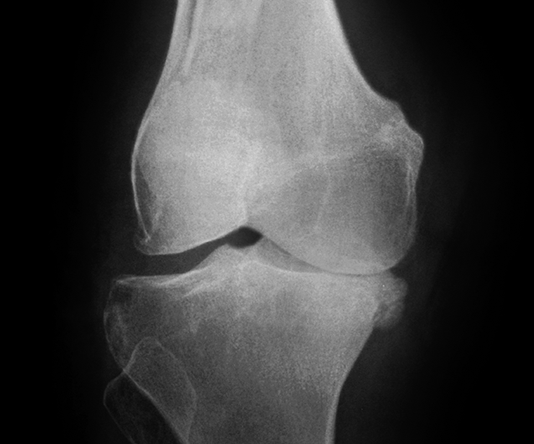

3. Giai đoạn 3: Thoái hóa khớp gối độ 3

Hình ảnh của khớp gối trên phim X-quang: Khe khớp hẹp rõ, nhiều gai xương kích thước vừa, đặc xương dưới sụn, đầu xương có thể bị biến dạng.

Thoái hóa khớp gối tiến triển đến giai đoạn 3

Thoái hóa khớp gối tiến triển đến giai đoạn 3 thì bệnh nhân sẽ càng cảm nhận rõ những cơn đau tại khớp gối. Các lớp sụn khớp bao bọc các đầu xương bị bào mòn nhiều và khoảng không gian giữa các đầu xương bị thu hẹp thấy rõ. Khả năng đi bộ của người bệnh giảm, đi, đứng, ngồi xổm, lên xuống cầu thang cũng thấy đau. Tình trạng cứng khớp vào buổi sáng cũng xảy ra thường xuyên hơn kèm theo các đợt viêm khớp gối (sưng, đau, tràn dịch) hoặc có biểu hiện vẹo khớp gối.